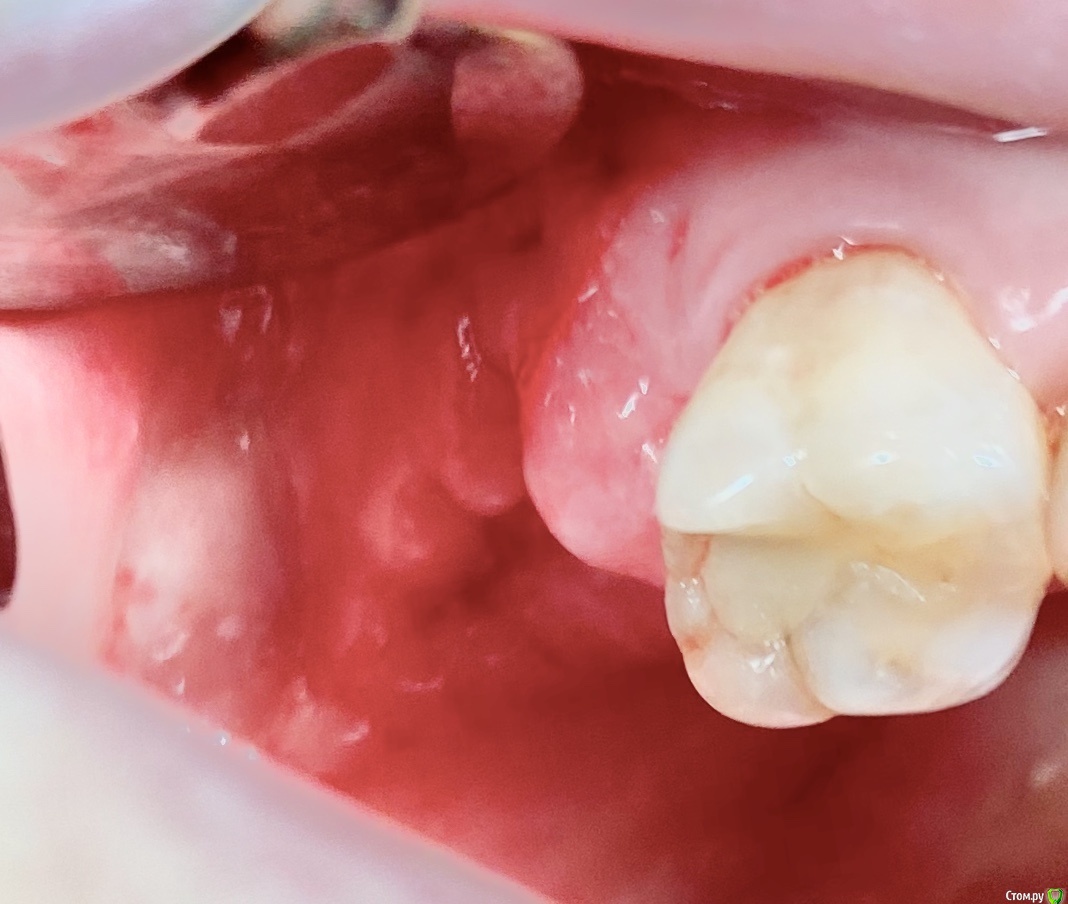

колесников Опубликовано 9 сентября, 2020 Поделиться Опубликовано 9 сентября, 2020 Бугор -это не только то ,что очевидно на поверхности 1 Ссылка на комментарий

колесников Опубликовано 11 сентября, 2020 Поделиться Опубликовано 11 сентября, 2020 Перемещение бугра для закрытия лунки. Вестибулярно прикрепленную не смещаем. Вестибулярно компактной пластинки нет 9 Ссылка на комментарий